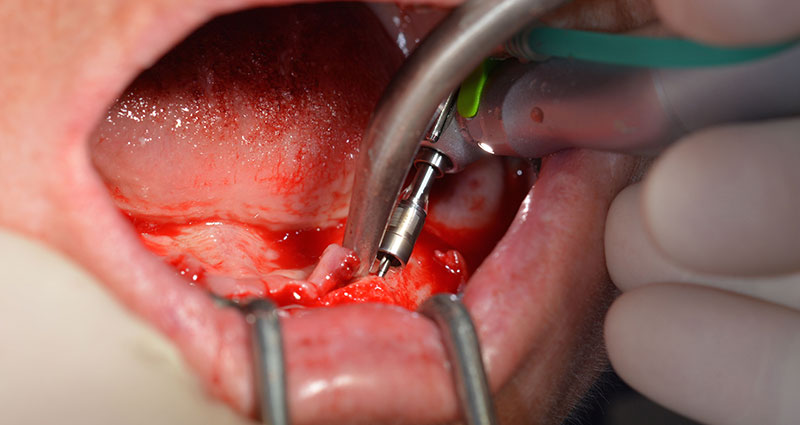

This corresponds to the next preset position in the Implantmed. Here we see the W&H contra-angle handpiece being held at a 45° angle to mesiocaudal in the region of 45 in order to preserve the mental nerve. The mental foramen is used as the anatomic reference for all drilling in this region. The subsequent holes were drilled at a reduced speed of 300 rpm (Fig. 10 and 11).